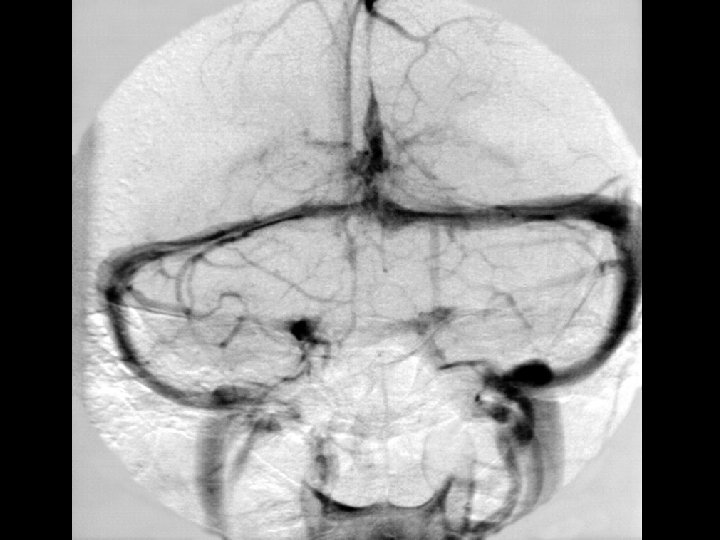

Angiographic digression to aid the understanding of venous angiography Michigan Neurosurgery

Early Venous phase Michigan Neurosurgery

Late Venous phase Michigan Neurosurgery